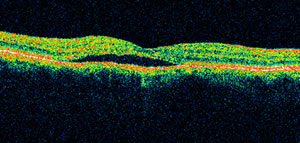

Ποιες ειδικές οφθαλμολογικές εξετάσεις πρέπει να γίνουν για την διάγνωση της νόσου;

Βυθοσκόπηση , OCT ωχράς , HRT 3 (Laser Scanning Tomography) ωχράς, Φλουοροαγγειογραφία κλπ. Οι παραπάνω εξετάσεις γίνονται με τα πιο σύγχρονα μηχανήματα στο οφθαλμολογικό κέντρο Bio Laser.